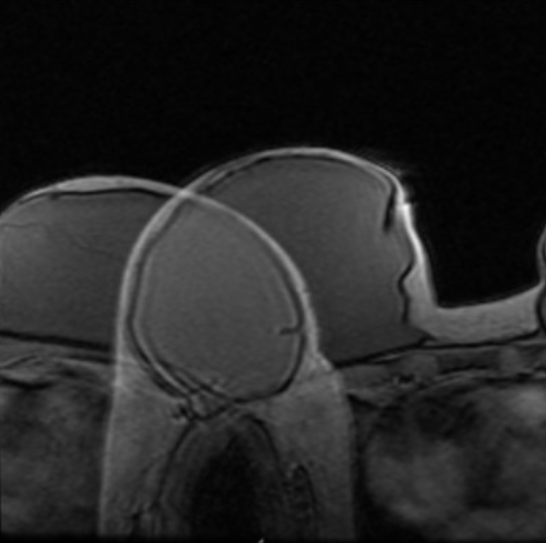

Wraparound artifact

caused by too small FOV